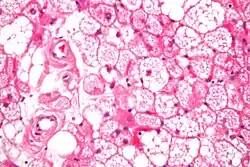

| Micrograph of a hibernoma. H&E stain. | |

The tumors histologically resemble brown fat. There are four histologic types recognized, but one is the most frequently seen (typical). There is a background of rich vascularity.

- Lobular type: Variable degrees of differentiation of uniform, round to oval cells with granular eosinophilic cells with prominent borders, alternating with coarsely multivacuolated fat cells (pale cells). There are usually small centrally placed nuclei without pleomorphism. The cells have large cytoplasmic lipid droplets interspersed throughout.[4][5]

- Myxoid variant: Loose, basophilic matrix, with thick fibrous septa, and foamy histiocytes

- Lipoma-like variant: Univacuolated lipocytes, with only isolated hibernoma cells

- Spindle cell variant: Spindle cell lipoma combined with hibernoma